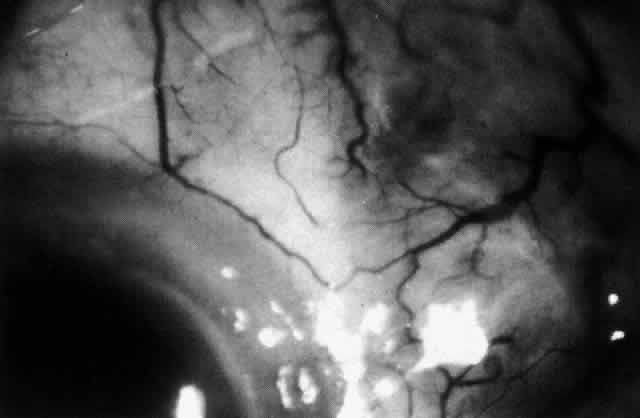

lower lid on attempted elevation of the eye (Fig. 54). Diagnosis is with B-scan ultrasonography.  Fig. 51. Swelling of the optic nerve head and hemorrhage near the disc in a patient

with posterior scleritis. The poor quality of the photograph is partly

due to vitreous haze that accompanied the inflammation. Fig. 51. Swelling of the optic nerve head and hemorrhage near the disc in a patient

with posterior scleritis. The poor quality of the photograph is partly

due to vitreous haze that accompanied the inflammation.

|